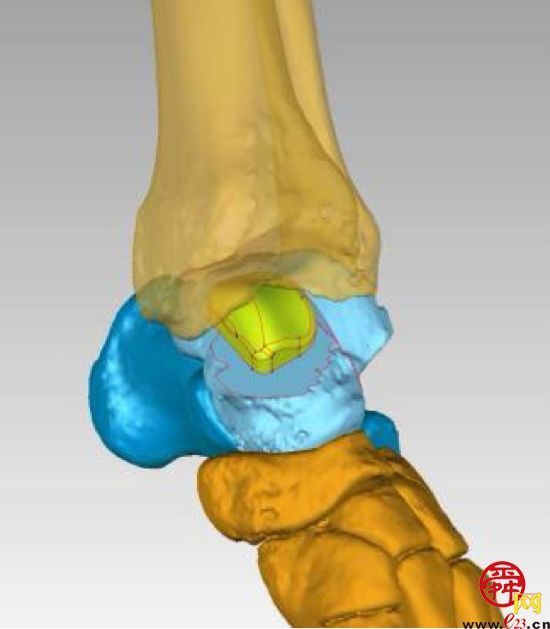

(术前3D打印设计)

手术在朱磊教授的指导下,由许庆家教授主刀,崔宜栋主治医师及刘奔医师作为助手实施完成。术中按照术前设计,将坏死距骨切除,置入设计好的3D打印的距骨半髁假体。术后指导患者早期功能锻炼,术后7天患者顺利出院。